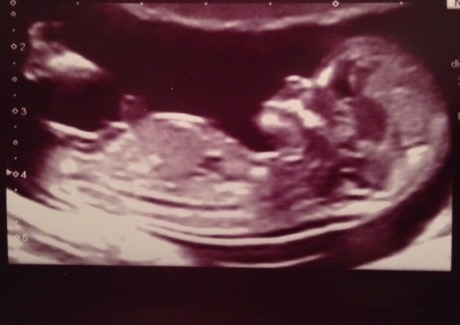

Biffle yes will be finding out been reading up the nub theory and I just don't get it they all look different to me!! Dh is convinced girl, Dd wants a sister and ds wants a brother so one of them will be disappointed!! Might book a 4d scan for 17 weeks yes I'm that inpatient to find out lol!!! I've found one on Groupon for £49 with dvd and pics thought that was really good

belle I was going on skull theory rather than nub. Girls have a more rounded forehead and certainly held true for my 3 looking back over scans. I'm so impatient to find out and really want to know! 20 week scan is roughly 22nd Jan (no date yet) and have to wait for DH to get home on 18th March before I can open envelope! It's going to kill me!!!